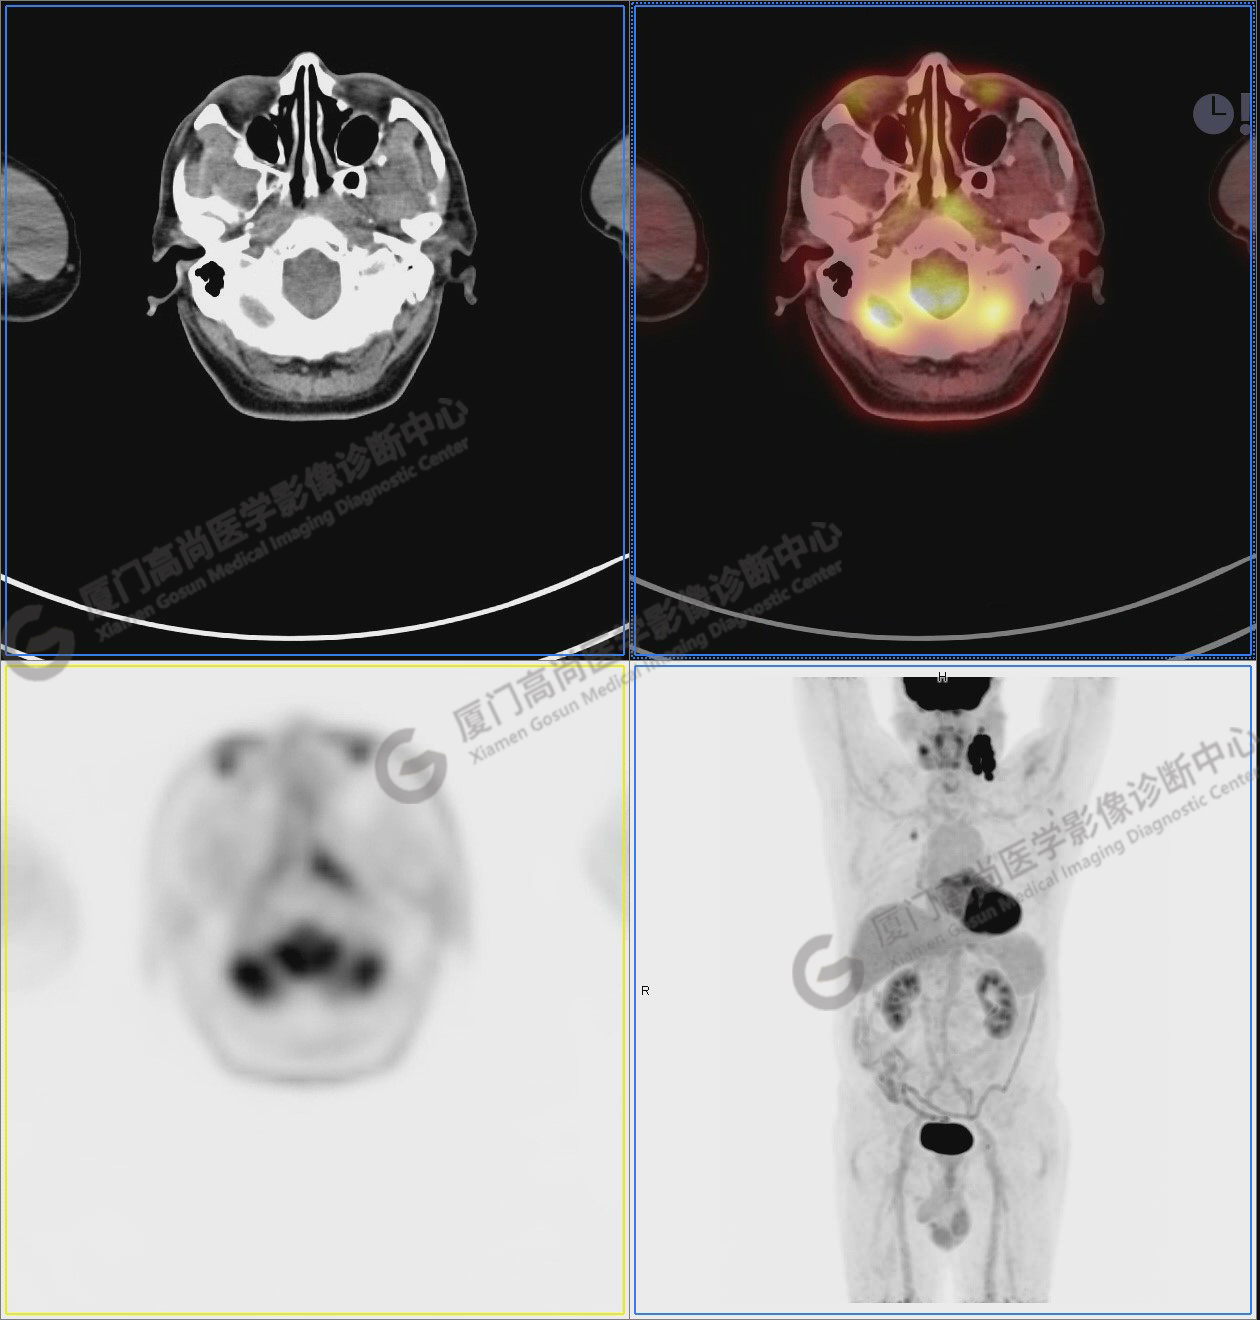

圖6-9:鼻咽左側(cè)壁增厚,代謝異常增高,考慮為鼻咽癌

圖6

圖7

圖8

圖9